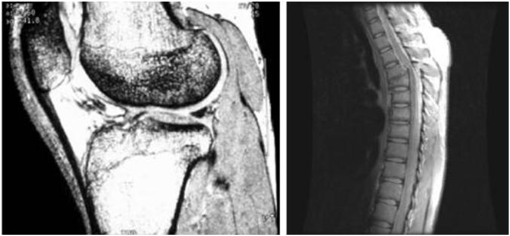

Imaging in the radio band

• 주요 응용분야: 의학(MRI: magnetic resonance image), 천문학

Image

인체의 MRI 무릎, 척추